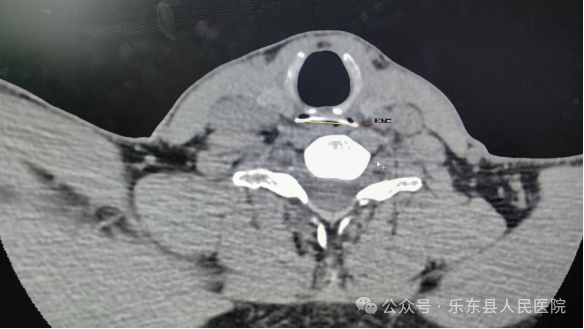

患者刘先生因误吞鹅骨,1小时后带着剧烈咽痛与异物感紧急就医。海医二院派驻专家卢大松副主任医师迅速响应,在喉内镜检查无果的情况下,凭借多年临床经验,从患者吞咽时的明显胸痛中捕捉到关键线索——”高度怀疑食管异物!”他立即启动绿色通道,亲自护送患者进行急诊食管三维CT检查,影像结果精准锁定“罪魁祸首”:食管入口处尖锐骨片赫然显现!